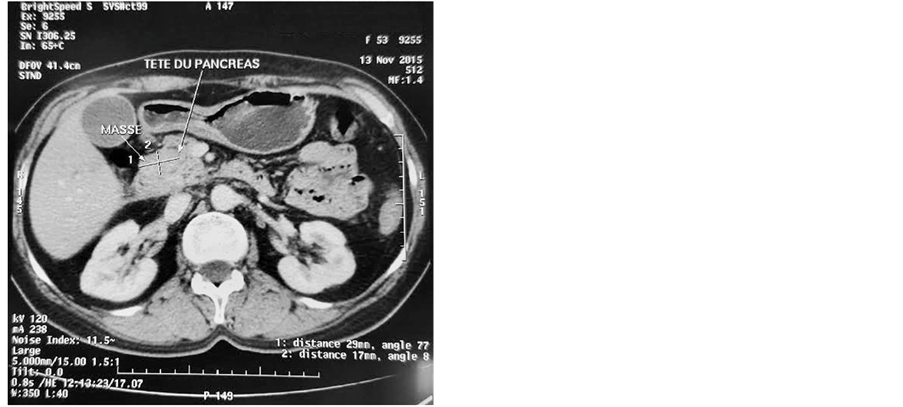

In November 2015, a 51-year-old female was referred to the emergency room in our institution due to cholangitis. Laboratory tests showed increased total and conjugated hyperbilirubinemia (52 mg/dl and 43 mg/dl, respectively). A CT scan showed a common bile duct tumor invading the duodenum (Figure 1), in addition to spread nodules in the lungs.

Figure 1.CT images of a common bile duct tumor invading the duodenum. (a) Mass centered on the lower part of the common bile duct, independent from the pancreas; (b) Tumoral thickening of the duodenal wall reflecting an invasion of the latter; (c) Dilation of the common bile duct (arrow head). The pancreatic duct is not dilated which confirms the tumor localization.